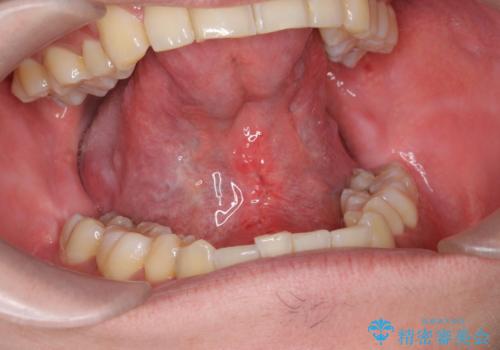

[ 舌小帯の形成 ]滑舌を改善したい

担当医 大元洋佑

![[ 舌小帯の形成 ]滑舌を改善したいの症例 治療前](https://seimitsushinbi.jp/wp/wp-content/uploads/2021/09/e82a05ecd2a75f6b35110889550d902d-500x350.jpg?v=1632645492)

![[ 舌小帯の形成 ]滑舌を改善したいの症例 治療後](https://seimitsushinbi.jp/wp/wp-content/uploads/2021/09/cdb65d722cca59883dfba72633174864-500x350.jpg?v=1632645504)